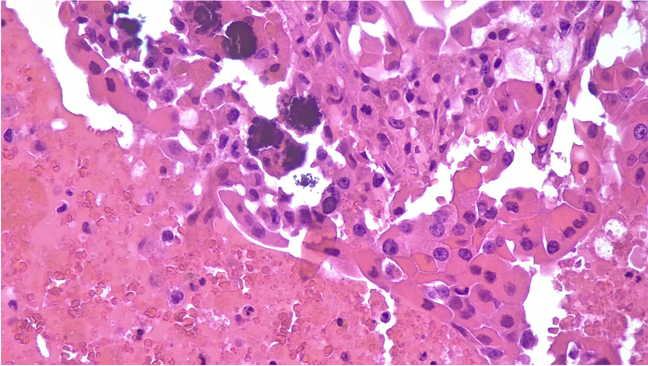

The diagnoses included 12 adenomas (one follicular and 11 oncocytic adenomas, Fig. 1A–B and Fig. 3), two chronic lymphocytic thyroiditis (HT) including one case with extensive oncocytic metaplasia, and 12 cases of thyroid follicular nodular disease (TFND) (Table 1, Fig. 2). In 24 of 26 cases, the thyroid parenchyma was entirely included at various levels, to find sub-centimeter PTC which had been missed in the first evaluation (Table 2). In the remaining two cases (one oncocytic adenoma, one follicular nodular disease), the nodules with psammoma bodies were entirely embedded (Fig. 3). None was found to harbor carcinoma after detailed sectioning. None of the patients have shown any evidence of thyroid carcinoma on follow-up.

Fig. 1

A, B The pictures show an oncocytic adenoma with evidence and details of psammoma bodies within the lesion (H&E, 200 ×)

The picture shows the details of psammoma bodies in the contest of oncocytic cells in a case diagnosed as oncocytic adenoma (H&E, 400 ×)